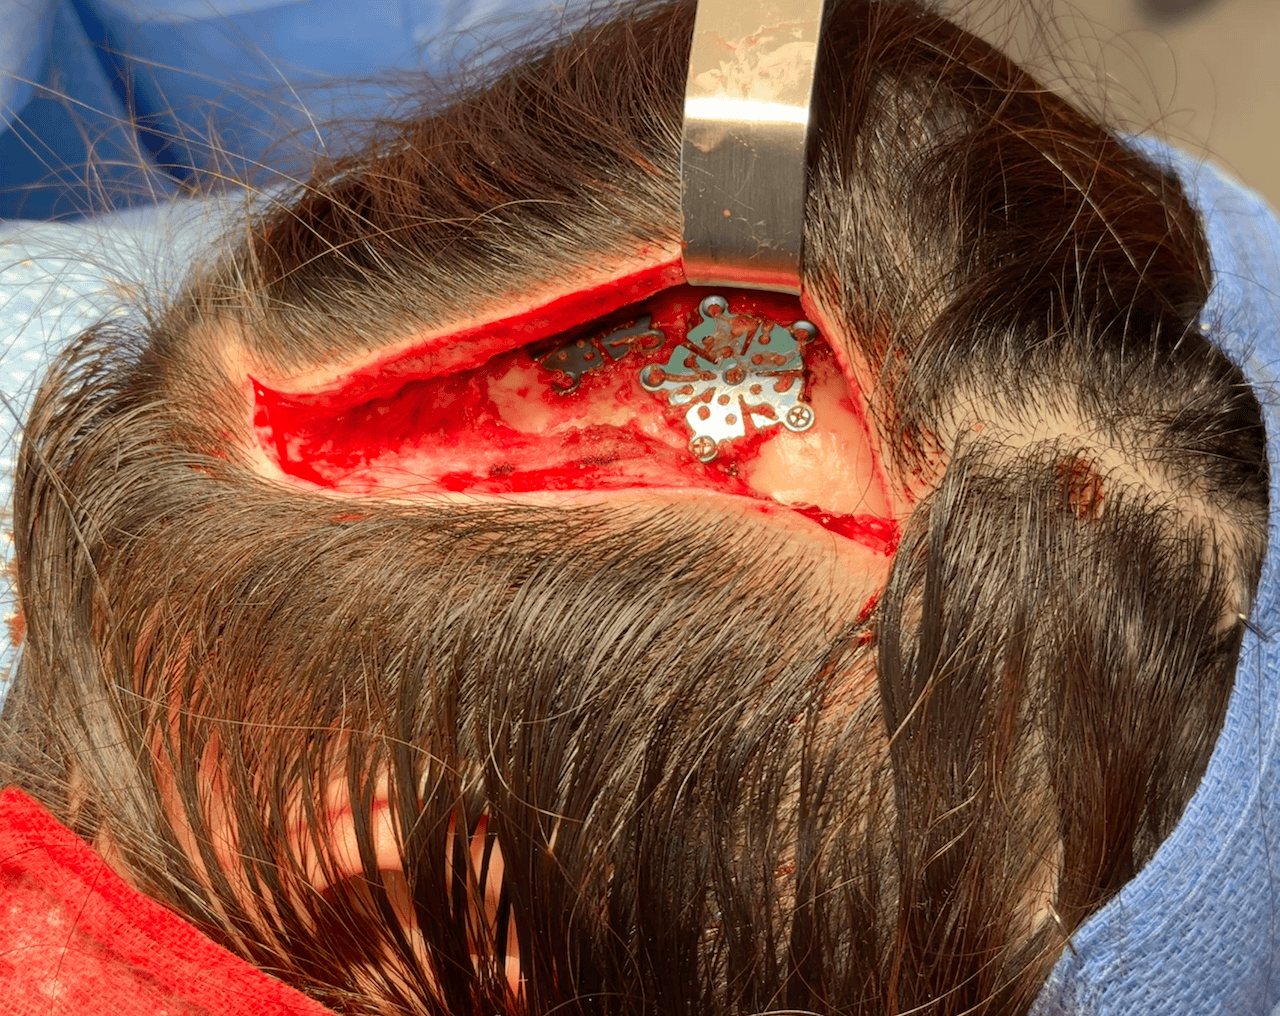

Left temporal skull defect from prior craniotomy.

Left temporal skull reconstruction with titanium mesh and hydroxyapatite cement.

Left temporal skull defect from prior craniotomy.

Left temporal skull reconstruction with titanium mesh and hydroxyapatite cement.